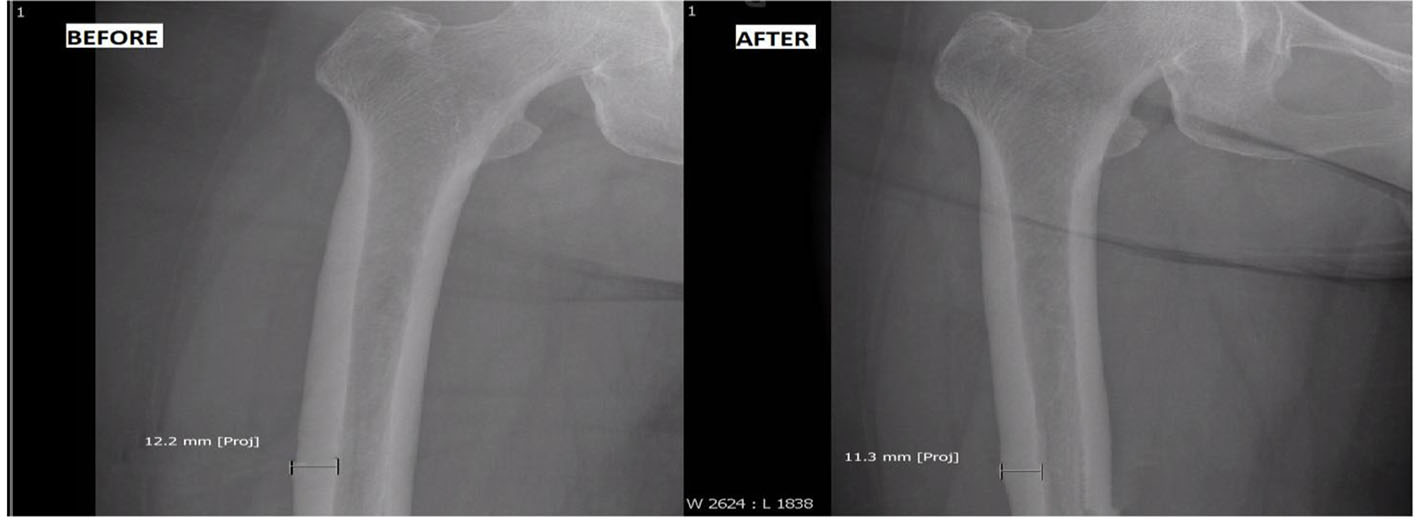

BP was discontinued, and she was started on once daily subcutaneous injection of TPP (Forteo®, 600 μg/2.4 mL). She was followed every 3 months with femur radiographs. During treatment course, her right thigh and low back pain gradually subsided. In addition, repeat BMD of her lumbar vertebrae revealed significant improvement with T score of -0.4 (1.128 g/cm2), and femoral neck showed stable T score (-2.1; 0.749 g/cm2) (Table 1). Radiograph of her symptomatic right femur revealed reduction in cortical thickening from 12.2 to 11.3 mm after a full 2-year course of TPP (Fig. 1).

![]() Click for large image | Figure 1. Before: cortical thickening of 12.2 mm before teriparatide use; after: reduction of cortical thickening to 11.3 mm after teriparatide use. |